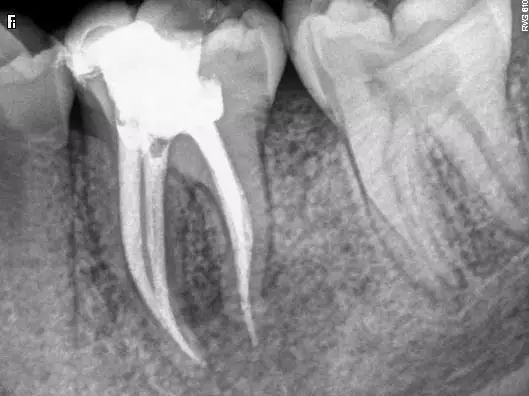

4)根管欠填或超填

良好的根管充填是适填,无论是去髓术或根管治疗,只要根管经过有效的药物消毒,允许少量欠填或超填(0.5~1.0㎜)。但如欠填过多,近根尖孔处形成死腔,可能导致组织液滞留,尤其是根尖周有炎症者,带有细菌的液体回流积聚,可继续成为感染源,使根尖周病变难以愈合。而超填过多的牙胶尖难以被组织吸收,同样会影响病变的愈合。